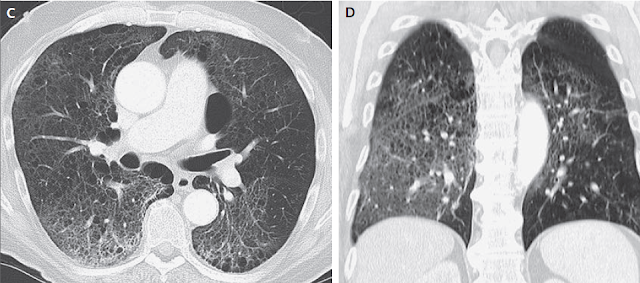

Figura 1

Estudios por imágenes de los senos paranasales y órbitas.

RMN DE ÓRBITAS REALIZADA EN OTRO HOSPITAL. Una imagen en T2 (Panel A)y una T1 con contraste (Panel B) muestra tejido de densidad intermedia tapizando el seno esfenoidal y afectando el vértice de la órbita izquierda y el seno cavernoso (flechas). Un corte coronal en T1 (Panel C) muestra realce de partes blandas extendiéndose inferiormente al foramen oval. Una TC de órbita (Panel D) muestra que el hueso entre el seno esfenoidal y el vértice de la órbita están relativamente intactos a pesar de la presencia de tejido con densidad de partes blandas anormal a ambos lados (flecha).

TC de las órbitas (Figura 1D) reveló que el hueso entre el tejido blando anormal en el seno esfenoidal izquierdo y el tejido blando anormal en el vértice de la órbita izquierda estaba prácticamente intacto.